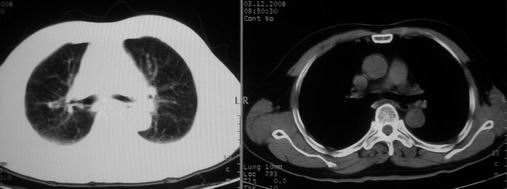

男,78岁,咳嗽、咳痰、发热入院,抗炎治疗一周后已退热,咳血似痰。

10月9日片: